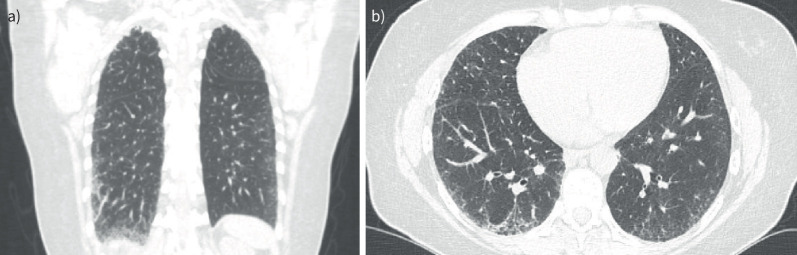

A non-resolving cough in a 41-year-old woman: a case of familial pulmonary fibrosis.

Identification of cases of familial pulmonary fibrosis is important with the risk of a monogenic cause. Patients appear to be younger and may have a more progressive disease. Consideration for antifibrotics and early transplant referral should be made. https://bit.ly/42jJ3aO.